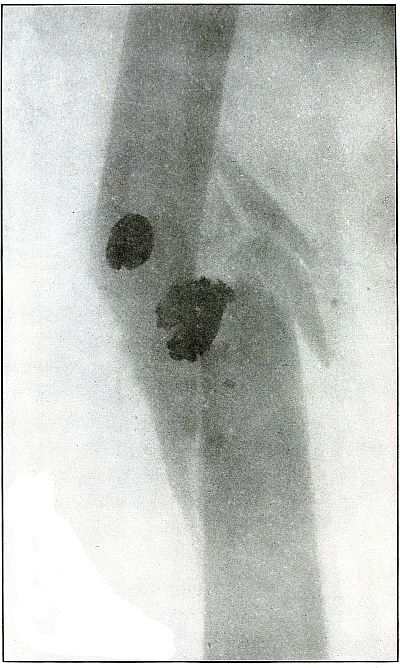

| 59. |

Gunshot wound, knee |

128 |

| 60. |

| 128.[Pg 6] |

Gunshot wound, knee |

266 |

| 129. |

Gunshot wound, knee |

268 |

| 130. |

Gunshot wound, knee |

270 |

| 131. |

Gunshot wound, knee |

272 |

| 132. |

Gunshot wound, knee |

274 |

| 133. |

Gunshot wound, knee |

276 |

| 134. |

Gunshot wound, knee |

278 |